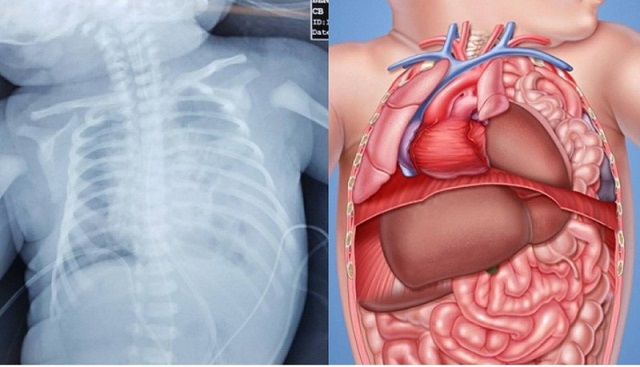

Click vào ảnh để xem 2 hình ảnh minh họa

Khiếm khuyết cơ thành bụng là một dạng khiếm khuyết bẩm sinh khiến cho dạ dày, ruột hoặc các cơ quan khác nhô ra thông qua lỗ mở bất thường trên bụng.

Có hai loại khiếm khuyết chính do thay đổi trong quá trình phát triển: thoát vị rốn và thoát vị thành bụng. Thoát vị thành bụng xuất hiện khi thành bụng không hoàn toàn đóng lại và các cơ quan ở bên ngoài cơ thể của trẻ sơ sinh. Viêm quanh niệu quản xảy ra khi một số cơ quan nhô qua các cơ vùng bụng xung quanh rốn. Khiếm khuyết cơ thành bụng có thể là một khiếm khuyết nhỏ, với một số phần bị phơi nhiễm hoặc nặng hơn, với gần như toàn bộ các cơ quan trong cơ thành bụng đều bị phơi nhiễm.